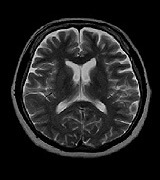

MRI画像

• mri01

• mri02

• mri03

• mri04